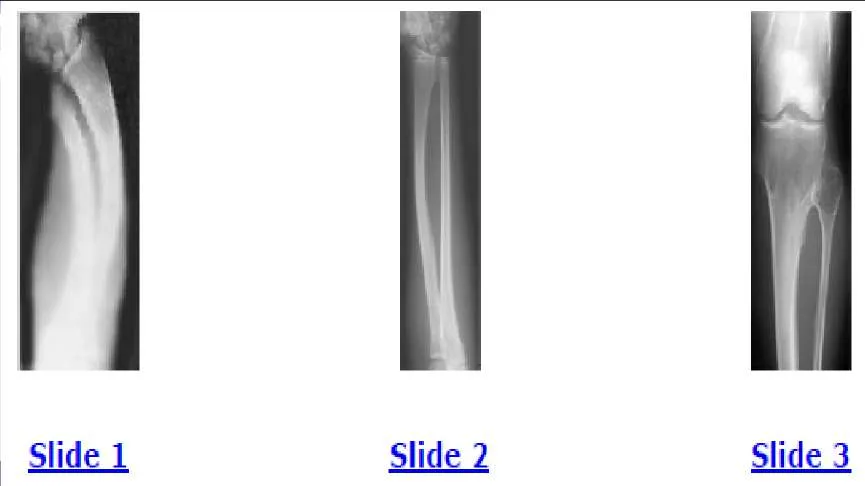

A 12-year-old boy is brought to the clinic by his concerned parents. The boyâ s forearm is bowed, and his parents are confused as to the possible diagnosis and treatment options. You notice that the right forearm of the child is bowed ulnarwards and is shorter compared to the left forearm. The pronosupination is markedly decreased on the right side but is also limited on the left side. The patient has a good grip, pinch, and grasp. He is neurologically intact as well. The parents say that they first noticed the deformity around 6 or 7 years ago, and the mother informs you that she had noticed a hard bump on the forearm. She has recently noticed another bump on his right leg. The child does not complain of pain and is using both of his hands quite well. The parents were informed by a previous physician that the child has Madelungs deformity and are concerned that the disease is now involving other areas of his body. An immediate appointment for magnetic resonance imagine (MRI) and computed tomography (C T) scan are not available, and a genetic evaluation has been carried out previously. As you await the report from the geneticist office, you decide to get a skeletal radiograph series on the patient. The radiograph of the opposite forearm (Slide 1) and right leg are shown (Slide 2). You order a radiograph of the forearm. The anteroposterior radiograph is shown (Slide 3). Your suspected diagnosis is:

A 12-year-old boy is brought to the clinic by his concerned parents. The boys forearm is bowed, and his parents are confused as to the possible diagnosis and treatment options. You notice that the right forearm of the child is bowed ulnarwards and is shorter compared to the left forearm. The pronosupination is markedly decreased on the right side but is also limited on the left side. The patient has a good grip, pinch, and grasp. He is neurologically intact as well. The parents say that they first noticed the deformity around 6 or 7 years ago, and the mother informs you that she had noticed a hard bump on the forearm. She has recently noticed another bump on his right leg. The child does not complain of pain and is using both of his hands quite well. The parents were informed by a previous physician that the child has Madelungs deformity and are concerned that the disease is now involving other areas of his body. You order a radiograph of the forearm. The anteroposterior radiograph is shown (Slide 1). The childâ s skeletal radiograph survey is also presented (Slide 2 and Slide 3). The genetic pattern seen in patients with this type of presentation is:

A 12-year-old boy is brought to the clinic by his concerned parents. The boy s forearm is bowed, and his parents are confused as to the possible diagnosis and treatment options. You notice that the right forearm of the child is bowed ulnarwards and is shorter compared to the left forearm. The pronosupination is markedly decreased on the right side but is also limited on the left side. The patient has a good grip, pinch, and grasp. He is neurologically intact as well. The parents say that they first noticed the deformity around 6 or 7 years ago, and the mother informs you that she had noticed a hard bump on the forearm. She has recently noticed another bump on his right leg. The child does not complain of pain and is using both of his hands quite well. The parents were informed by a previous physician that the child has Madelungs deformity and are concerned that the disease is now involving other areas of his body. You order a radiograph of the forearm. The anteroposterior radiograph is shown (Slide 1). The childâ s skeletal radiograph survey is also presented (Slide 2 and Slide 3). Which of the following areas is unlikely to be involved:

A 12-year-old boy is brought to the clinic by his concerned parents. The boyâ s forearm is bowed, and his parents are confused as to the possible diagnosis and treatment options. You notice that the right forearm of the child is bowed ulnarwards and is shorter compared to the left forearm. The pronosupination is markedly decreased on the right side but is also limited on the left side. The patient has a good grip, pinch, and grasp. He is neurologically intact as well. The parents say that they first noticed the deformity around 6 or 7 years ago, and the mother informs you that she had noticed a hard bump on the forearm. She has recently noticed another bump on his right leg. The child does not complain of pain and is using both of his hands quite well. The parents were informed by a previous physician that the child has Madelungâ s deformity and are concerned that the disease is now involving other areas of his body. You order a radiograph of the forearm. The anteroposterior radiograph is shown (Slide 1). The childâ s skeletal radiograph survey is also presented (Slide 2 and Slide 3). The chance of hand involvement in this child is:

A 12-year-old boy is brought to the clinic by his concerned parents. The boyâ s forearm is bowed, and his parents are confused as to the possible diagnosis and treatment options. You notice that the right forearm of the child is bowed ulnarwards and is shorter compared to the left forearm. The pronosupination is markedly decreased on the right side but is also limited on the left side. The patient has a good grip, pinch, and grasp. He is neurologically intact as well. The parents say that they first noticed the deformity around 6 or 7 years ago, and the mother informs you that she had noticed a hard bump on the forearm. She has recently noticed another bump on his right leg. The child does not complain of pain and is using both of his hands quite well. The parents were informed by a previous physician that the child has Madelungs deformity and are concerned that the disease is now involving other areas of his body. You order a radiograph of the forearm. The anteroposterior radiograph is shown (Slide 1). The childâ s skeletal radiograph survey is also presented (Slide 2 and Slide 3). The most likely complication in this child is:

A 12-year-old boy is brought to the clinic by his concerned parents. The boys forearm is bowed, and his parents are confused as to the possible diagnosis and treatment options. You notice that the right forearm of the child is bowed ulnarwards and is shorter compared to the left forearm. The pronosupination is markedly decreased on the right side but is also limited on the left side. The patient has a good grip, pinch, and grasp. He is neurologically intact as well. The parents say that they first noticed the deformity around 6 or 7 years ago, and the mother informs you that she had noticed a hard bump on the forearm. She has recently noticed another bump on his right leg. The child does not complain of pain and is using both of his hands quite well. The parents were informed by a previous physician that the child has Madelungs deformity and are concerned that the disease is now involving other areas of his body. You order a radiograph of the forearm. The anteroposterior radiograph is shown (Slide 1). The childâ s skeletal radiograph survey is also presented (Slide 2 and Slide 3). The difference between Madelungâ s deformity and this boyâ s condition is:

A 12-year-old boy is brought to the clinic by his concerned parents. The boys forearm is bowed, and his parents are confused as to the possible diagnosis and treatment options. You notice that the right forearm of the child is bowed ulnarwards and is shorter compared to the left forearm. The pronosupination is markedly decreased on the right side but is also limited on the left side. The patient has a good grip, pinch, and grasp. He is neurologically intact as well. The parents say that they first noticed the deformity around 6 or 7 years ago, and the mother informs you that she had noticed a hard bump on the forearm. She has recently noticed another bump on his right leg. The child does not complain of pain and is using both of his hands quite well. The parents were informed by a previous physician that the child has Madelungs deformity and are concerned that the disease is now involving other areas of his body. You order a radiograph of the forearm. The anteroposterior radiograph is shown (Slide 1). The childâ s skeletal radiograph survey is also presented (Slide 2 and Slide 3). All of the following are acceptable options, either alone or in combination, for management of this childâ s condition, except:

Question 46: